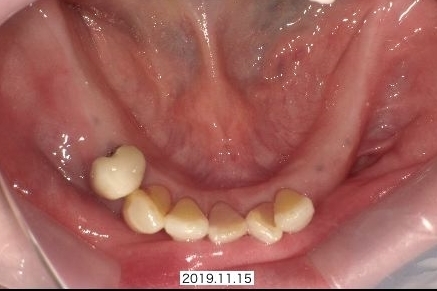

上あごの歯、下あごの奥歯(大臼歯・小臼歯)がないため、他院で取り外し式の入れ歯をつくりましたが、違和感が強く、長く使用していない状態でした。お食事や発音に不便を感じられ、奥歯でしっかり咬めるようになりたいとの希望で、当院のホームページをご覧になり来院されました。

上のご自分の歯は、虫歯や重度歯周病で3本抜歯が必要でした。

下のご自分の歯は、折れていた左下の歯がお痛みもあり、抜歯が必要でした。

上下に仮歯としての入れ歯がすでにはいっています。

早めに抜歯したため歯茎が治っています

最終的に、下あごのみインプラント治療を希望となりましたが、事前にすばやく抜歯+入れ歯セットを行っていたため、最終的なプランが固まるころには、抜歯した部位もきれいに治っており、インプラント手術もとてもスムーズに行うことができます。